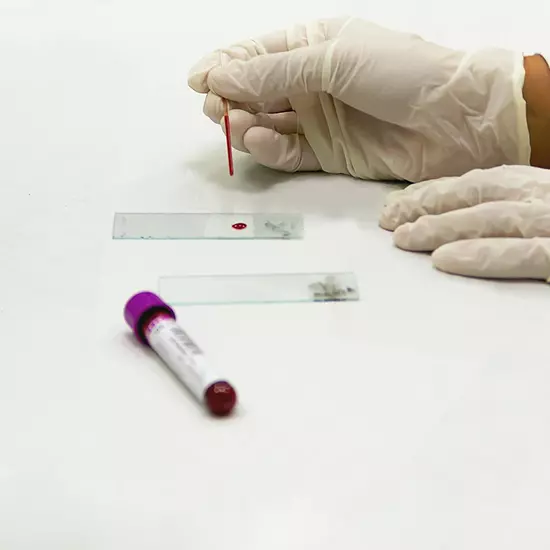

Experience Excellence in General Treatment at MedHC

Your health is our priority. From routine check-ups to specialized treatments, our experienced professionals are here to guide you every step of the way.